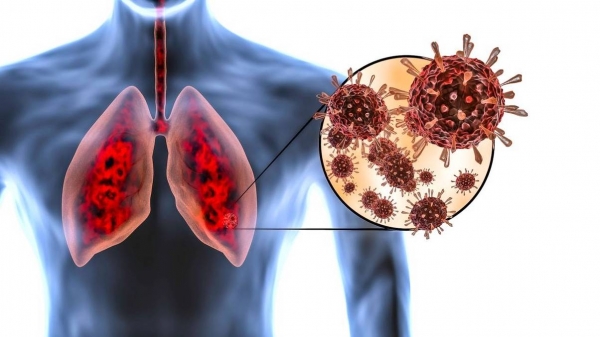

平日里,感染之后,潜伏期一般是4天至14天,最长能够到达45天,一开始的症状跟流感相似,有发热、头痛、肌肉酸痛以及乏力。部分患者会呈现出咳嗽、咽痛还有呼吸困难的状况。

有可能病情会迅猛发展成严重肺炎以及急性呼吸窘迫,脑炎属于典型且危险的并发症,呈现出嗜睡、意识混乱、抽搐乃至昏迷的状况,幸存者也许会出现长期神经后遗症,像是性格改变以及持续抽搐。